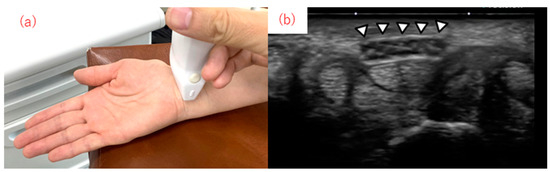

Dynamic Analysis of the Median Nerve in Carpal Tunnel Syndrome from Ultrasound Images Using the YOLOv5 Object Detection Model

- Huang, Y.T.; Chen, C.J.; Wang, Y.W.; Peng, P.L.; Luo, Y.T.; Horng, Y.S. Ultrasonographical Evaluation of the Median Nerve Mobility in Carpal Tunnel Syndrome: A Systematic Review and Meta-Analysis. Diagnostics 2022, 12, 2349. [Google Scholar] [CrossRef]